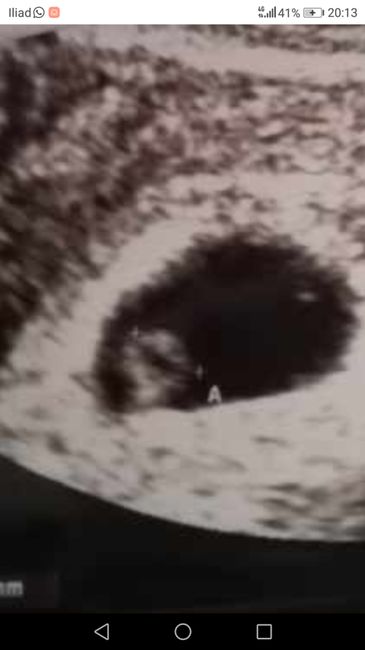

Buongiorno!! Chi è brava a spiegarmi il metodo Ramzi e sa azzeccarci? 😊

2233 giorni faCiao ragazze! Lunedì avrò la prima eco, sono spaventatissima!!! L'ansia comincia a frasi sentire e ho paura che sia presto e non si veda nulla. Io lunedì sarò a 6+0. Voi quando avete visto per la primo volta il vostro fagiolino?